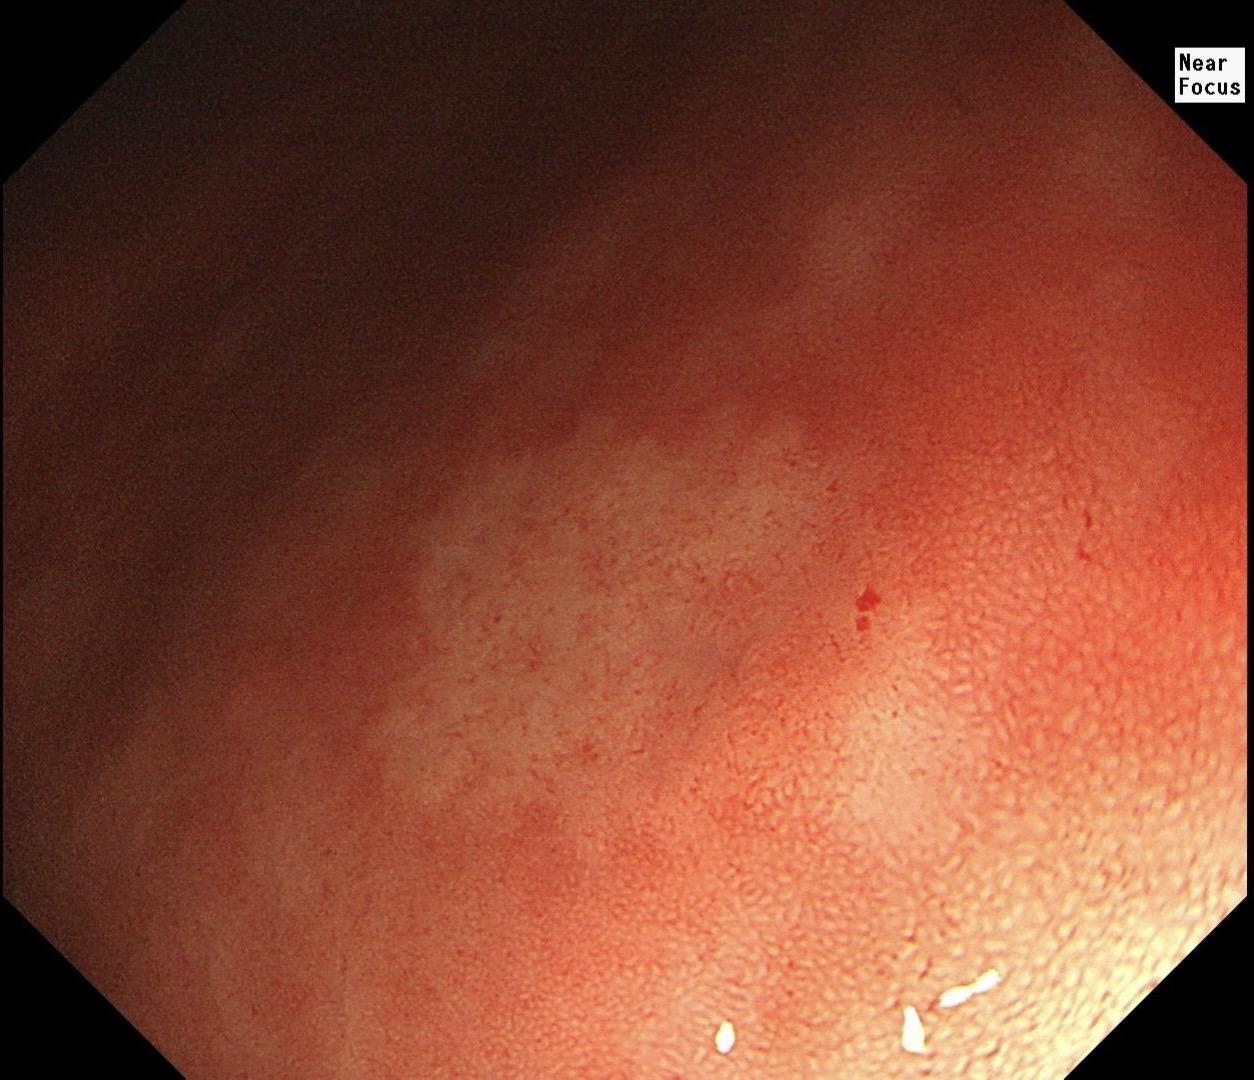

男,40岁,胃双发褪色调病变。慢性胃炎复查,3年前胃镜未见异常,Hp阳性背景,萎缩不明显,胃体下部大弯见一褪色调病变,浅凹陷,5mm左右,换用放大内镜观察,表面结构缺失,血管异型明显,未分化可能性大……胃窦后壁见一白斑,无高度差,NBI浅茶色,放大草草看了下,似有边界,IP增宽,活检待病理……小哥哥胖得几乎没脖子,腹式呼吸太明显~😖